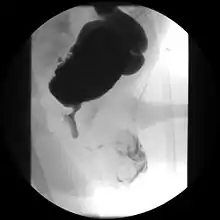

Cystourethrograph showing bladder obstruction with dilation of urethra and bladder

Ultrasound imaging can give information on the shape of the bladder, post-void residual volume, and evidence of kidney damage such as kidney size, thickness or ureteral dilation.[9] Trabeculated bladder on ultrasound indicates high risk of developing urinary tract abnormalities such as hydronephrosis and stones.[10] A voiding cystourethrography study uses contrast dye to obtain images of the bladder both when it is full and after urination which can show changes in bladder shape consistent with neurogenic bladder.[9]